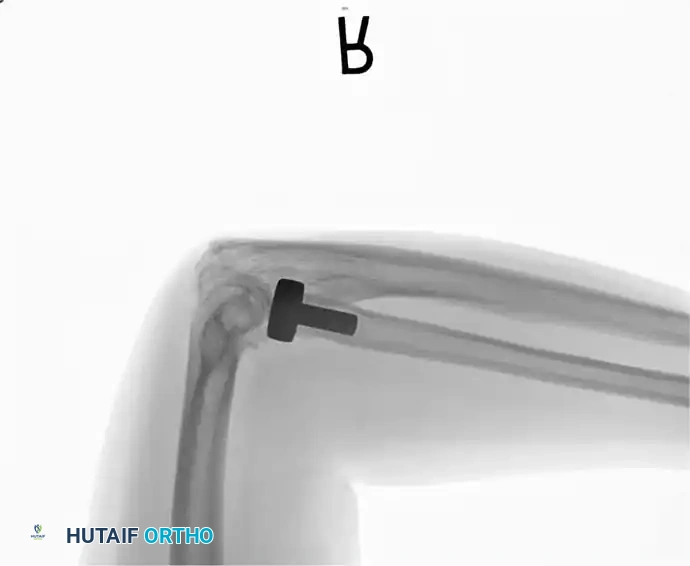

2. Intramedullary Fixation with Tension Band

If the fracture is more distal, or if there is a tendency for the proximal fragment to angulate posteriorly, a simple tension band wire is insufficiently stable. In these cases, intramedullary fixation (using Kirschner wires or a large cancellous screw) is combined with the tension band.

Kirschner Wires vs. Cancellous Screws:

* K-wires: The AO technique utilizes two parallel K-wires (1.6 mm or 2.0 mm) driven down the medullary canal. To prevent proximal migration, the K-wires must engage the anterior cortex of the ulna distal to the coronoid.

* Cancellous Screw: A biomechanical analysis by Murphy et al. demonstrated that a long 6.5-mm or 7.3-mm AO cancellous screw combined with a figure-of-eight wire provides a significantly stronger construct than K-wires. The screw must be long enough to achieve secure purchase in the ulnar diaphysis.

Fig. 54-55 Olecranon fracture repaired with long 6.5-mm AO cancellous screw and figure-of-eight tension band wire loop. Screw must engage cortex of diaphysis of ulna.

🔪 Surgical Technique: K-Wire and Tension Band (AO Technique)

- Reduction: Anatomically reduce the fragments and hold them temporarily with a reduction clamp.

- K-Wire Insertion: Introduce two parallel K-wires longitudinally from the tip of the olecranon across the fracture site. Direct them slightly anteriorly so they engage the anterior ulnar cortex distal to the coronoid process.

- Wire Loop: Pass an 18-gauge wire through a transverse drill hole in the distal fragment. Cross the wire in a figure-of-eight fashion over the posterior surface.

- Proximal Capture: Pass the wire around the protruding proximal ends of the K-wires.

- Double Twist: Weber and Vasey suggest twisting both limbs of the figure-of-eight loop. This double-twist modification ensures uniform compression across the fracture site.

- Securing K-wires: Bend the proximal ends of the K-wires 180 degrees, cut them short, and tap the bent ends deep into the triceps insertion and proximal bone to prevent symptomatic hardware prominence and migration.

Fig. 54-56 A and B, Transverse olecranon fracture repaired with Kirschner wires and tension band technique. C, Double twist modification of wiring suggested by Weber and Vasey.